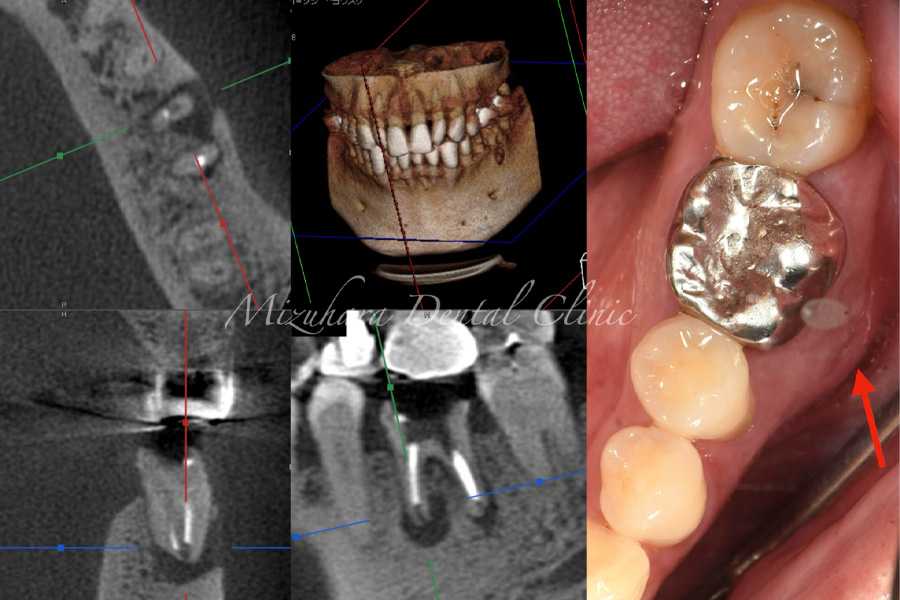

予知性の高い治療を提供できるだけ患者様の大切な歯を残し、10年、20年先まで健康な状態を保てるよう、長期的な視点で治療を計画します。そのために最も重要なのが、「診査」と「診断」です。的確な診断は精密な診査から生まれ、治療結果を大きく左右します。問診や簡易検査だけでは見逃されがちな病変も、CTやマイクロスコープなどの最新の医療機器を活用し、時間をかけて丁寧に「診査・診断」を行います。

完全個室の診療室マイクロスコープをはじめ、歯科用CT、EMSエアフローや口腔内スキャナーによる光学印象など最新の医療機器を完備し、精密で質の高い歯科医療を提供します。

世界基準の成功率を目指した精密根管治療

当院では豊マイクロスコープ、ラバーダムを使用し、世界基準の成功率を目指した精密根管治療による「歯を残す」ための治療をご提供します。